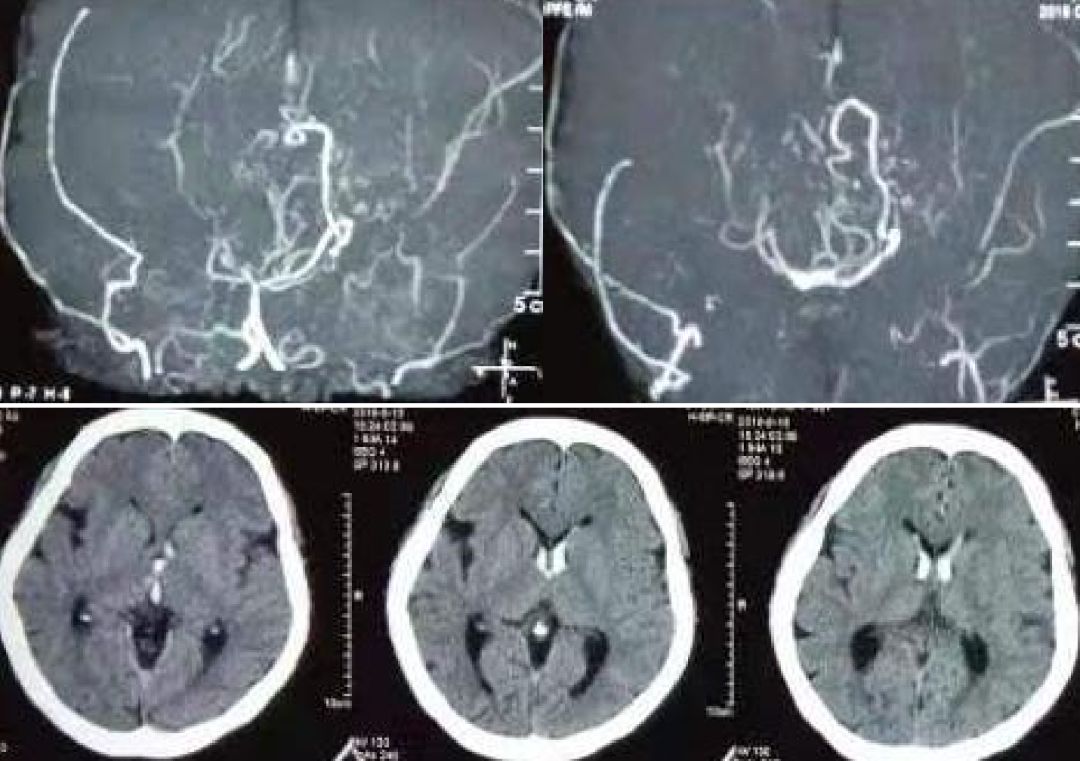

病例10

女性,52岁。头痛、恶心、呕吐4小时入院,既往有高血压、糖尿病。

答案:烟雾病。

好多老师认为脑室出血,不理解为什么是烟雾病。患者本次入院行MRA及CT平扫图像如下:

烟雾病和烟雾综合征的临床表现复杂多样。脑缺血最为常见,可表现为短暂性脑缺血发作(transient ischemic attack,TIA)、可逆性缺血性神经功能障碍(reversible ischemic neurologic deficit,RIND)或脑梗死,其中TIA常由情绪紧张、哭泣、剧烈运动或进食热辣食物等诱发。自发性颅内出血多见于成年患者,主要原因是烟雾状血管或合并的微动脉瘤破裂出血,以脑室内出血或脑实质出血破入脑室最为常见,也可见基底节区或脑叶血肿,单纯蛛网膜下腔出血较少见。神经功能障碍与脑缺血或颅内出血部位等相关。其他临床表现还包括认知功能障碍、癫痫、不随意运动或头痛等。